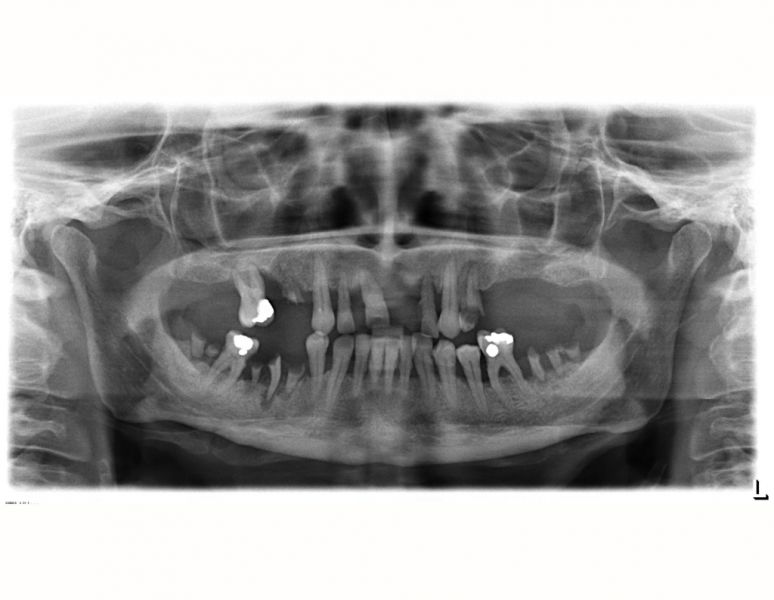

- zhotovování panoramatických RTG snímků

- zhotovování 3D RTG snímků

Zkratka CBCT neboli celým názvem „cone beam computed tomography“ je zobrazovací rentgenologické vyšetření, které zachycuje zvolený objem tkání ve všech rovinách – tedy 3D a umožňuje získat prostorový přehled a tím pádem dokonalejší zhodnocení vyšetřovaného objektu. Rozdíl oproti klasickému „nemocničnímu“ CT je ve zdroji záření a v detekci záření.

Klasické CT využívá tzv. vějířovitý RTG paprsek, který je detekován na relativně úzký detektor. Vznikající obraz je skládán po jednotlivých vrstvách (řezech) v závislosti na velikosti snímané plochy a velikosti CT detektoru. Velikost snímané plochy je několikanásobně větší než velikost detektoru. Proto RTG paprsek klasického CT přístroje rotuje v tzv. spirálách okolo snímaného pacienta několikanásobně vícekrát pro pořízení 3D snímků v porovnání s CBCT.

CBCT rentgeny využívají tzv. kuželovitý RTG paprsek (CB = Cone Beam = kuželovitý paprsek), který je detekován na široký (čtvercový/obdélníkový) detektor. Velikost detektoru je vždy dostatečně velká pro pokrytí celé velikosti snímané plochy, díky čemuž stačí pouze jediná 360° rotace okolo pacienta pro požadovaný 3D rentgenový snímek. Díky této technologii disponují CBCT přístroje nespornou výhodou několikanásobně nižší radiační dávky (podle výrobců až 50x nižší), detailnější rozlišitelností snímků a rychlejšího vyšetření.

Své uplatnění nalezne bezesporu v endodoncii, tedy ošetření kořenových kanálků zubů – možnost přesného zhodnocení jejich průběhu a množství a tím pádem možnost následného kvalitnějšího ošetření, nebo v implantologii – zhodnocení množství a denzity(kvality) kosti, před zavedením kostního implantátu, a tím pádem precizní možnost volby velikosti Vašeho implantátu. Zapomenou nesmíme ani na možnost zhodnocení průběhu důležitých anatomických struktur před extrakcí zejména dolních třetích molárů – zubů moudrosti či v jiných specifických případech.

CBCT přístroj je tedy samozřejmě nedílnou součástí našeho přístrojového vybavení. Jedná se o přístroj nové generace s výjimečnou kvalitou snímku spojenou s nejnižší možnou dávkou záření.